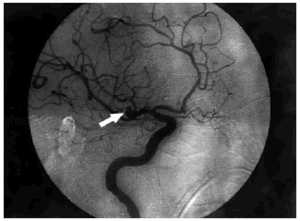

El ECG inicial, realizado en el servicio de urgencias, puso de manifiesto un ritmo sinusal de 80 lat/ min, con un QTc de 384 ms y datos de lesión subepicárdica anterior con elevación del ST más marcada en V2-3, I y aVL y descenso del ST en III y aVF (fig. 1, ECG 1). La tomografía axial computarizada (TAC) realizada a su ingreso objetivó una HSA de predominio en la cisura silviana derecha y en la arteriografía realizada a las 16 h se visualizó un aneurisma de 5 mm de diámetro en la bifurcación de la arteria silviana derecha (fig. 2).

Fig. 2. Arteriografía cerebral: aneurisma de 5 mm de diámetro (flecha) en la bifurcación de la arteria cerebral media derecha.